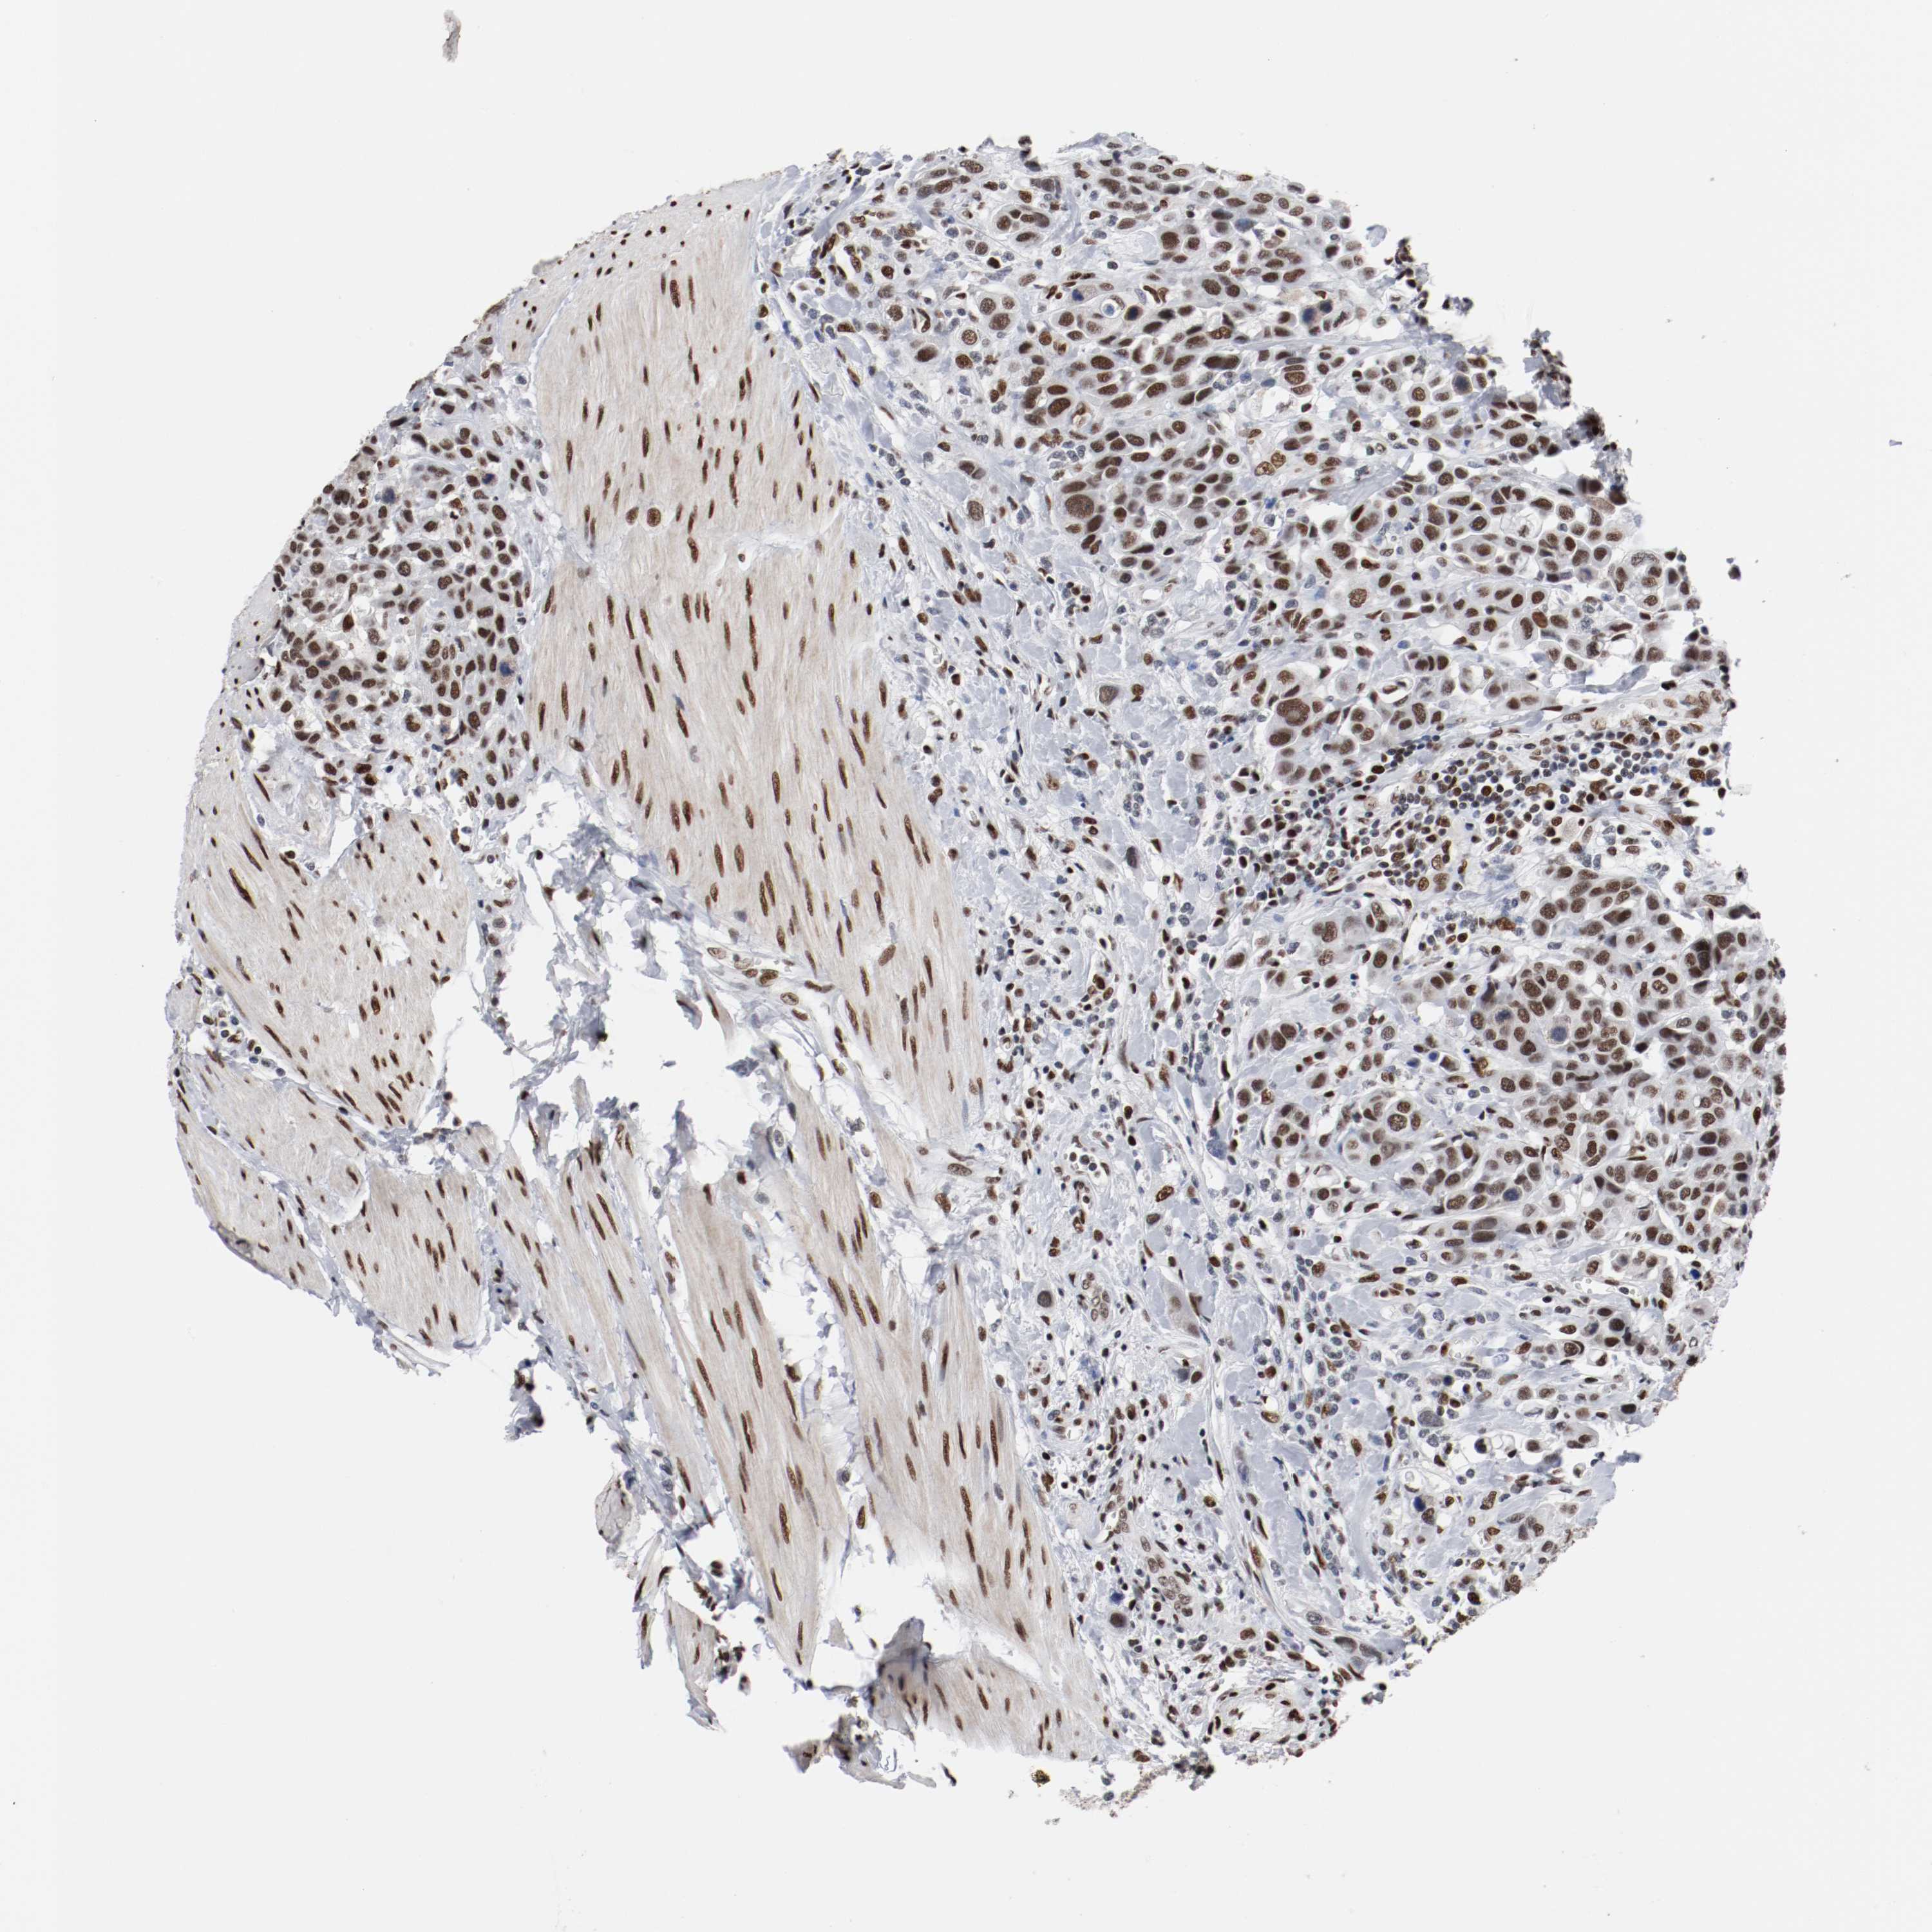

UROTHELIAL CANCER - Protein expressioni

A mouse-over function shows sample information and annotation data. Click on an image to view it in a full screen mode. Samples can be filtered based on level of antibody staining by selecting one or several of the following categories: high, medium, low and not detected. The assay and annotation is described here.

Antibody stainingi

Antibody staining in the annotated cell types in the current human tissue is reported as not detected, low, medium, or high, based on conventional immunohistochemistry profiling in selected tissues. This score is based on the combination of the staining intensity and fraction of stained cells.

Each image is clickable and will lead to virtual microscopy that enables deeper exploration of all samples and also displays staining intensity scores, fraction scores and subcellular localization as well as patient and tissue information for each sample.

Antibody HPA004807

Antibody HPA007114

Staining

High

Medium

Low

Not detected

Intensity

Strong

Moderate

Weak

Negative

Quantity

>75%

75%-25%

<25%

None

Location

Nuclear

Cytoplasmic/membranous

Cytoplasmic/membranous,nuclear

Urothelial carcinoma, High grade

Urothelial carcinoma, Low grade